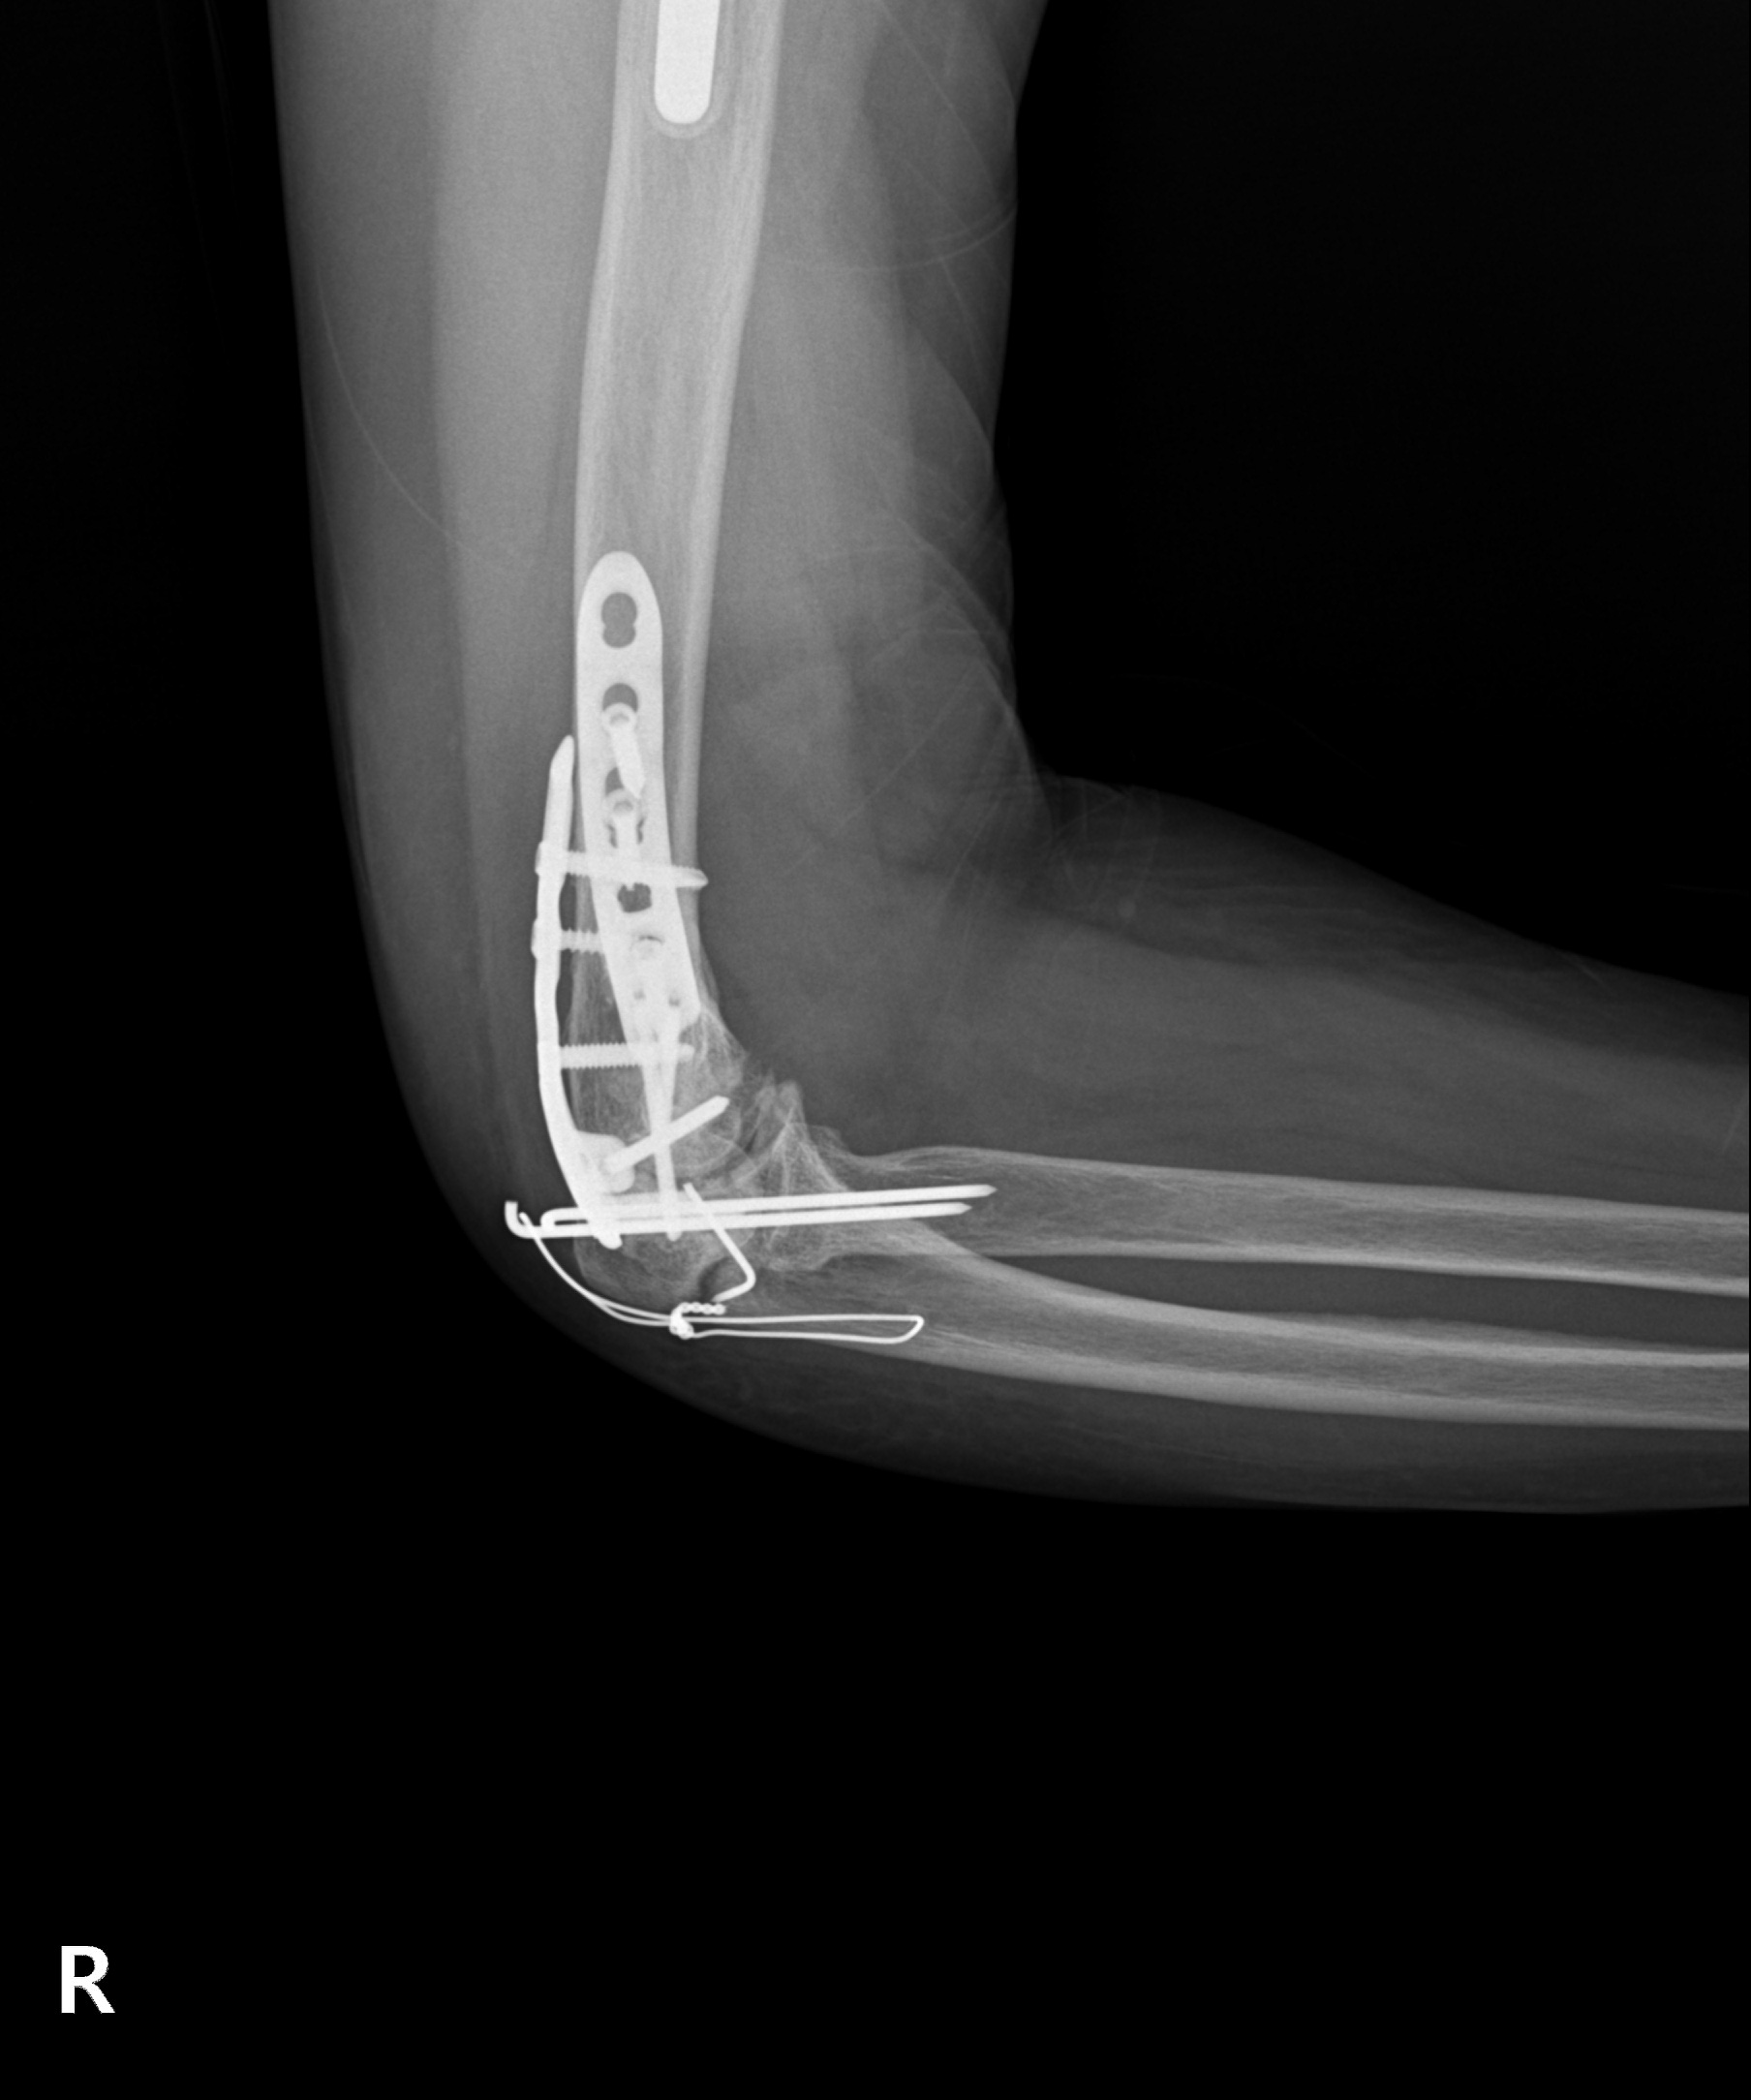

원위 상완골 골절

2022.07.14

2023.02.07